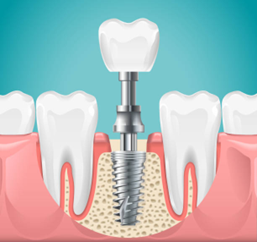

Single Tooth Implants

Designed to replace a single missing tooth, these implants are placed without disturbing surrounding teeth. A titanium post is inserted into the jawbone, topped with a natural-looking crown for seamless integration.